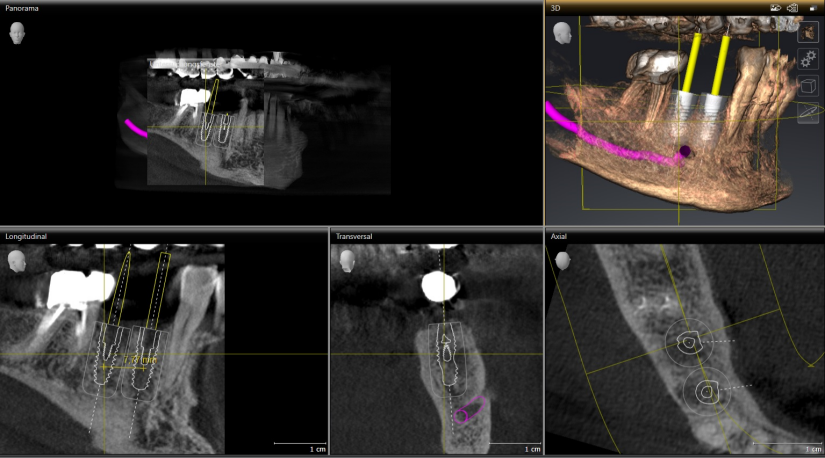

DVT – Digitale Volumentomographie

Mit Hilfe einer digitalen Volumentomographie (dreidimensionales Röntgen) haben wir die Möglichkeit, eine sehr detaillierte Diagnostik als Grundlage für die Behandlungsplanung nutzen zu können. Die Aufnahme wird in wenigen Sekunden angefertigt, wobei die Software aus mehreren hundert Einzelaufnahmen ein 3-dimensionales Bild der gewünschten Kieferabschnitte errechnet. Damit erreichen wir eine bisher in dieser Form noch nicht dagewesene Planungs- und Behandlungssicherheit.

Dabei handelt es sich um ein sehr breites Spektrum an nutzbaren  Informationen. Beginnend bei der Erkennung von verdeckten Entzündungsherden über die gezielte  Planung von Implantatversorgungen bis hin zu einer frühzeitigen Darstellung von Erkrankungen des Kieferknochens.